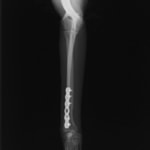

トイプードル 右遠位橈尺骨短斜骨折のALPSによる内固定

Locking Compression Plate

LCPは、スクリュー(ネジ)とプレート(金属の板)をロックする特殊な構造により骨折部位を固定する新しい世代のプレートシステムです。ひとつのホールでロッキングスクリューとスタンダードスクリューの使用を選択できるユニークな構造をしているため、骨折断端間の圧迫を目的とした従来型プレート固定法に加え、高い角度安定性を有するロッキングスクリューを用いた固定法の選択が可能です。従来のプレートシステムでは困難だった部分の骨折や癒合不全の症例に高い治療効果をもたらします。

当院ではAdvanced Locking plate system(ALPS)と、Locking compression plate system(LCPS)という骨接合法で骨折症例の治療を行っています。